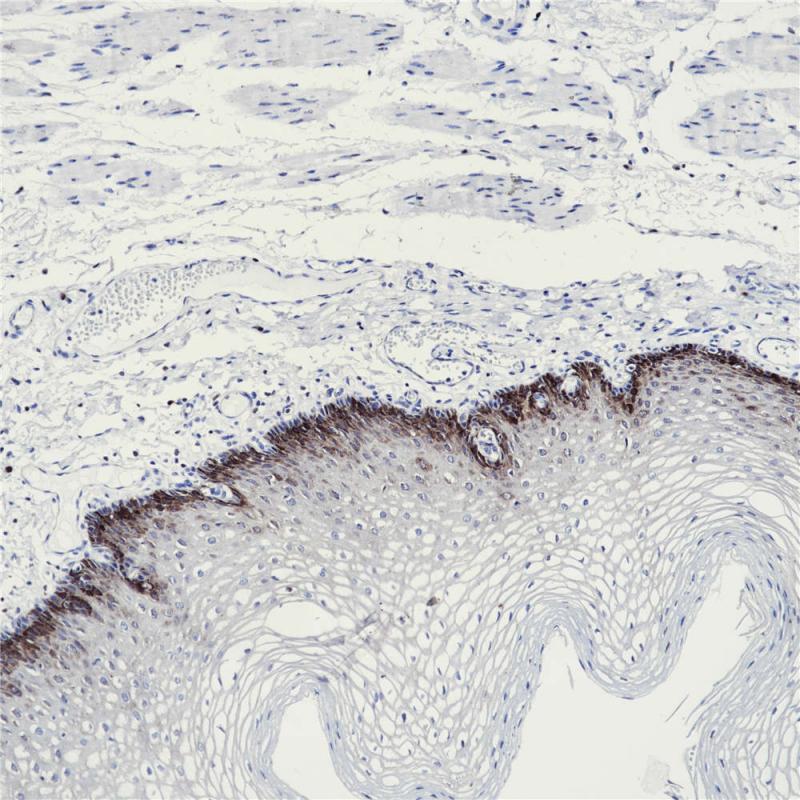

核苷二磷酸还原酶大亚基(RRM1)是组成核苷二磷酸还原酶的两个不同的亚基中的一个,是核苷酸的主要结合位点,通过 PTEN 诱导来控制癌细胞转移倾向,多应用于非小细胞肺癌的诊断。

阳性对照

乳腺癌

亚细胞定位

细胞质